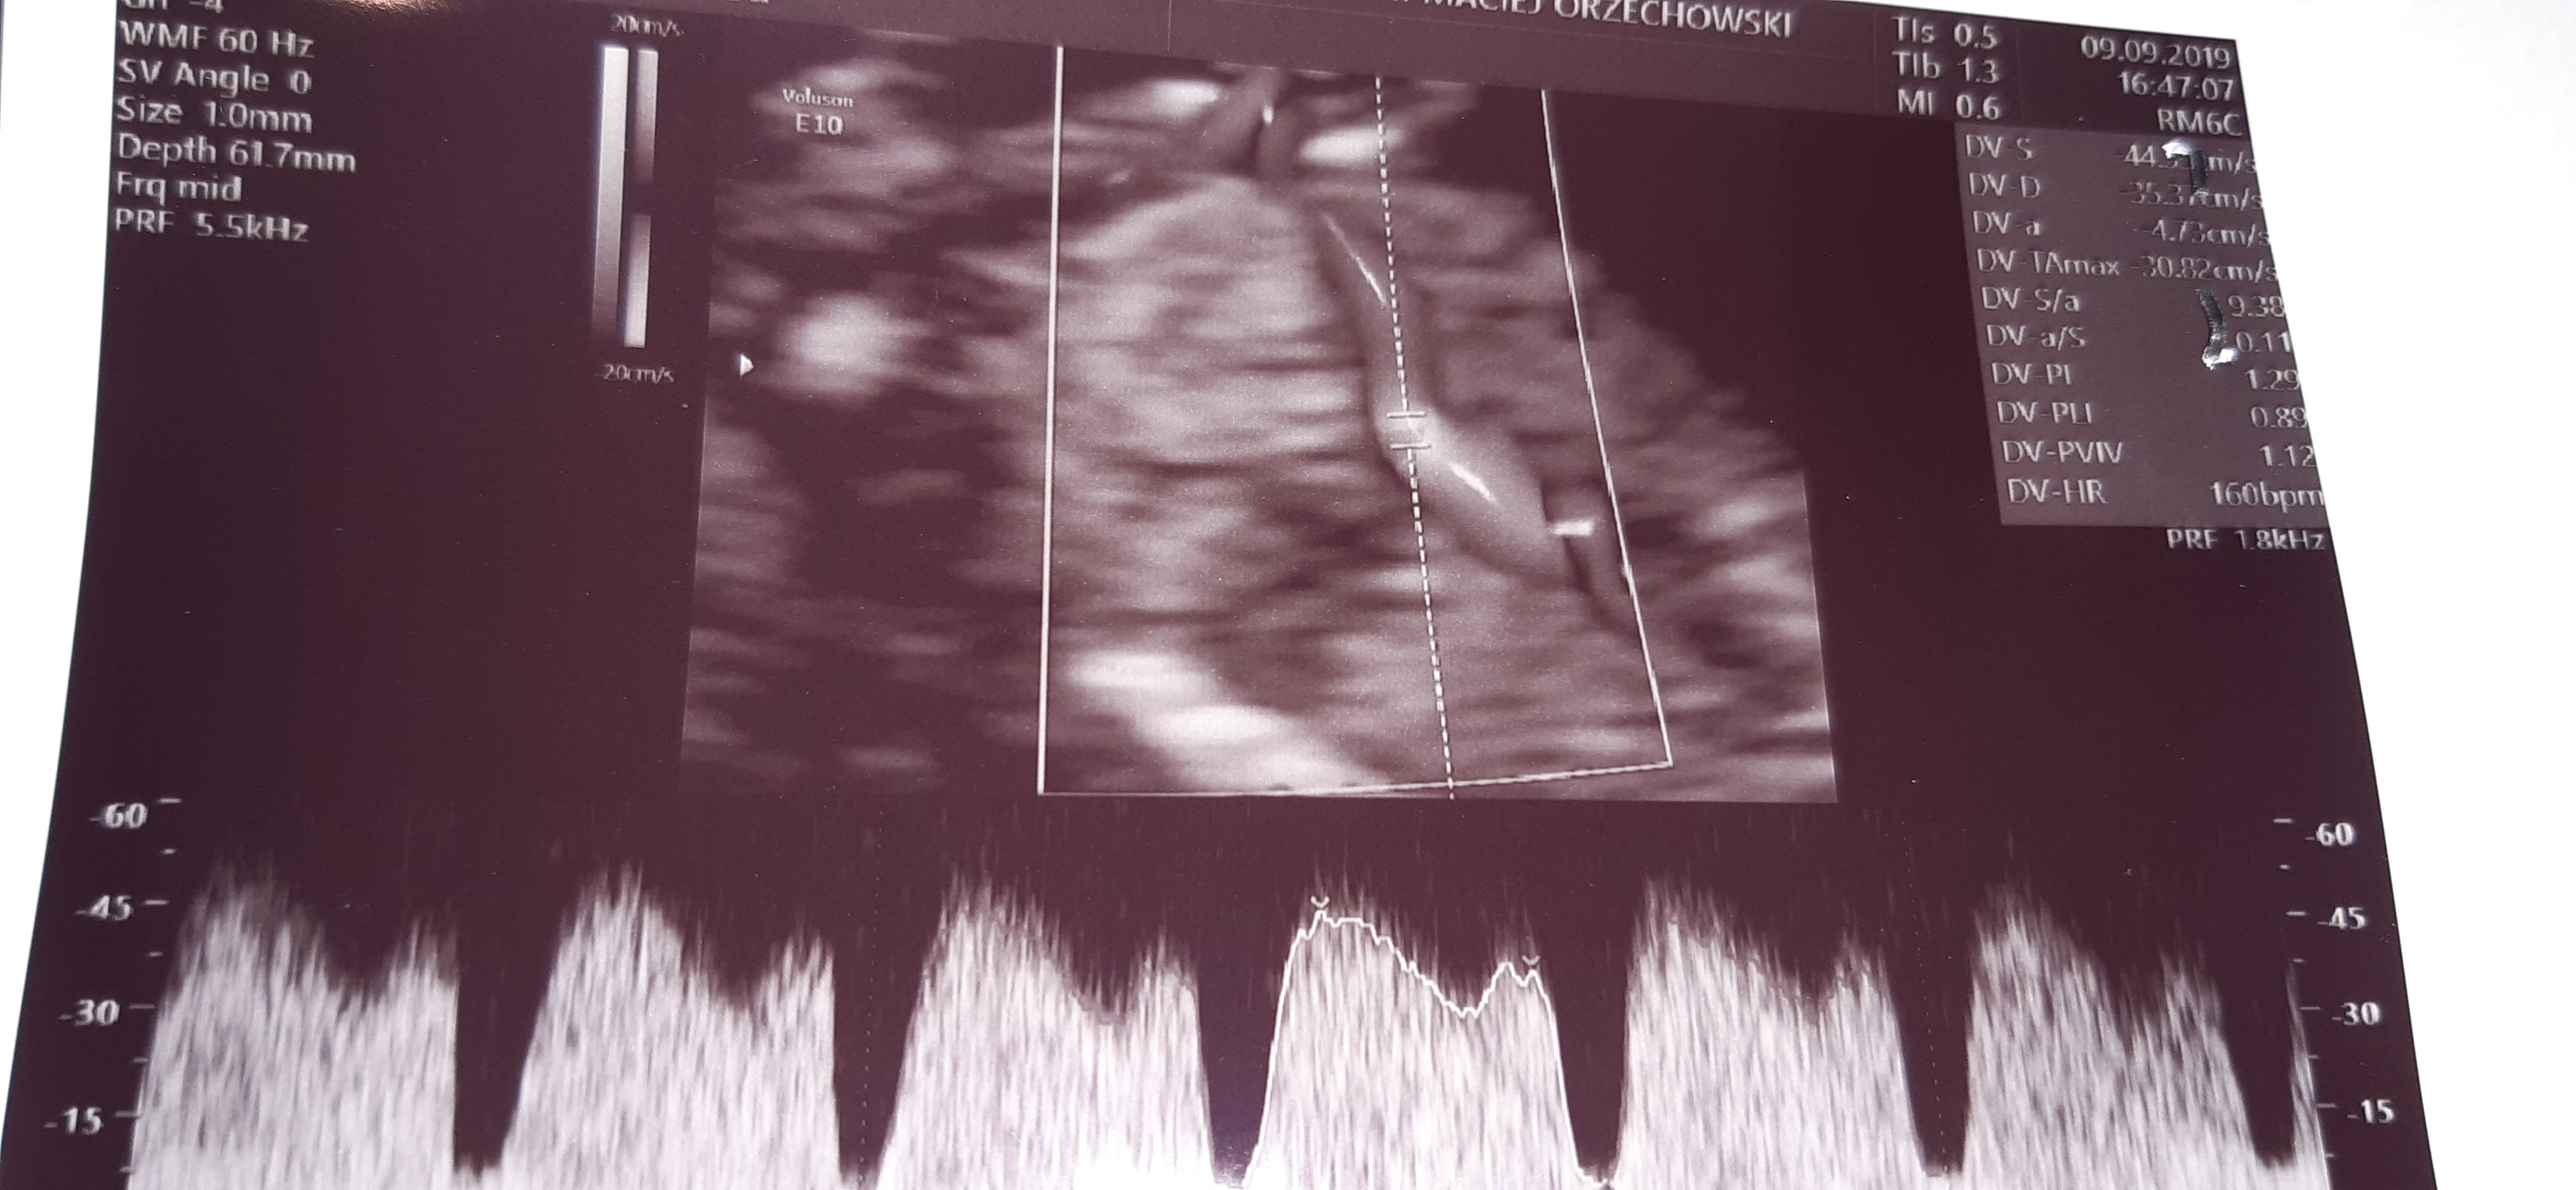

Nie mam pojęcia, ja mam DV PI równo 1. A masz jeszcze zdjęcia przepływów tętnic macicznych?

Jak wejdziesz na stronę badaniaprenatalne.pl to tam są informacje o badaniu 11 - 14 są piękne zdjęcia z badań i tak po środku jest o przyplywach DV i jest zdjęcie prawidłowe przepływy, kliknij i wyskoczy zdjęcie podobne do twojego gdzie. A zdjęciu jest napisane DV PI 1, 23 :)